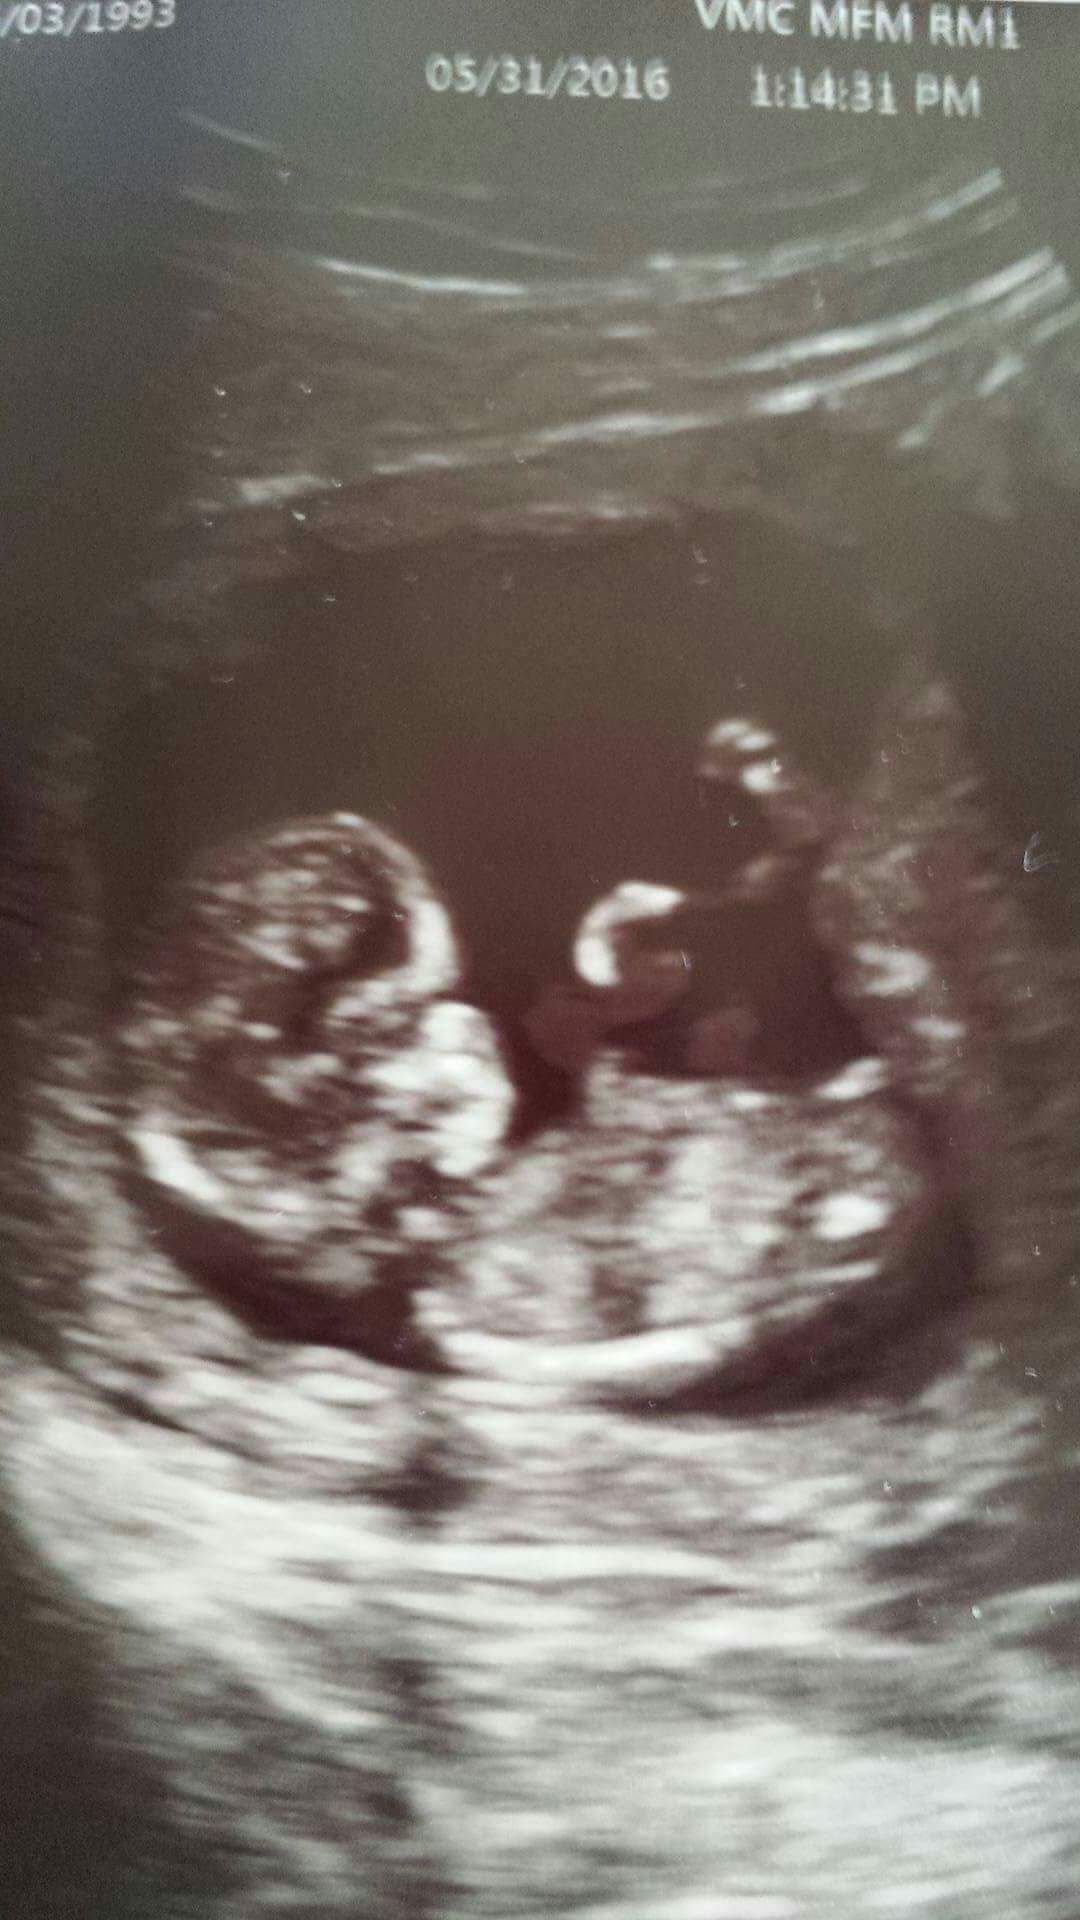

12w2d, I've been told it's a hard one! But just for fun, we'really tallying up all the guesses! We'd love as many opinions as possible! TIA!

I feel the bright parts are the legs? Not sure if I see anything between

I guess boy